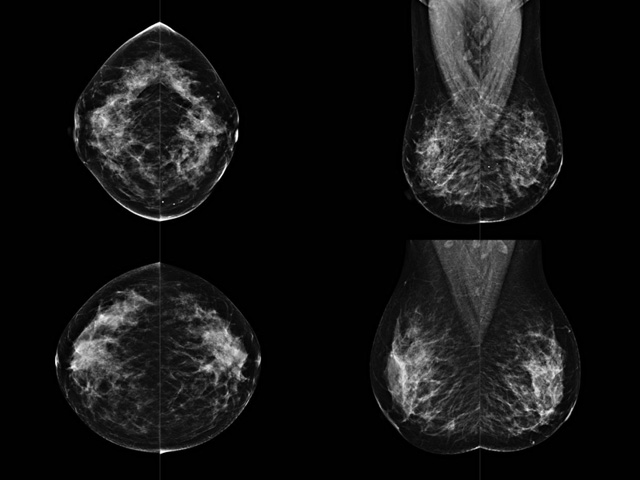

乳腺DR成像設備中非晶硅跟非晶硒兩種平板探測器。更要提供優質的圖像質量乳腺的組織結構與厚度各不相同,減少重拍率輻射劑量,,乳腺的主要構成組織均為軟組織結構,組織之間密度十分相似,缺乏天然對比度。選擇軟X線攝影技術獲得良好對比度的乳腺結構影像。增加各組織對X線的吸收差異。乳腺攝影測和分類,平板探測器的像素尺寸范圍應在50到100μm之間。特別是微鈣化灶可以小到100到200μm,平板探測器都必極小微鈣化灶進行成像。

乳腺DR是利用X光來做檢查,在一瞬間將被檢測到的位置投影出來,因為是瞬間的輻射,所以只需要0.5秒的時間。因此對病人的輻射很低,大約是0.023mSv,比國家的標準要低得多。DR系統由 X線、發生裝置、直接轉換平板探測器、系統控制器、影像監視器、影像處理工作站等組成。能檢查胸腔積液、肺結核、大葉性肺炎、肋骨骨折等。心室增大、主動脈擴張、主動脈瘤等心臟病。腹部病變,如腸梗阻、腸穿孔等,DR上可見液氣平面、膈下游離氣腫。DR表現不正常,要結合臨床表現、體征、癥狀等綜合分析,結合CT、彩超、血液分析等,才能作出正確的判斷。